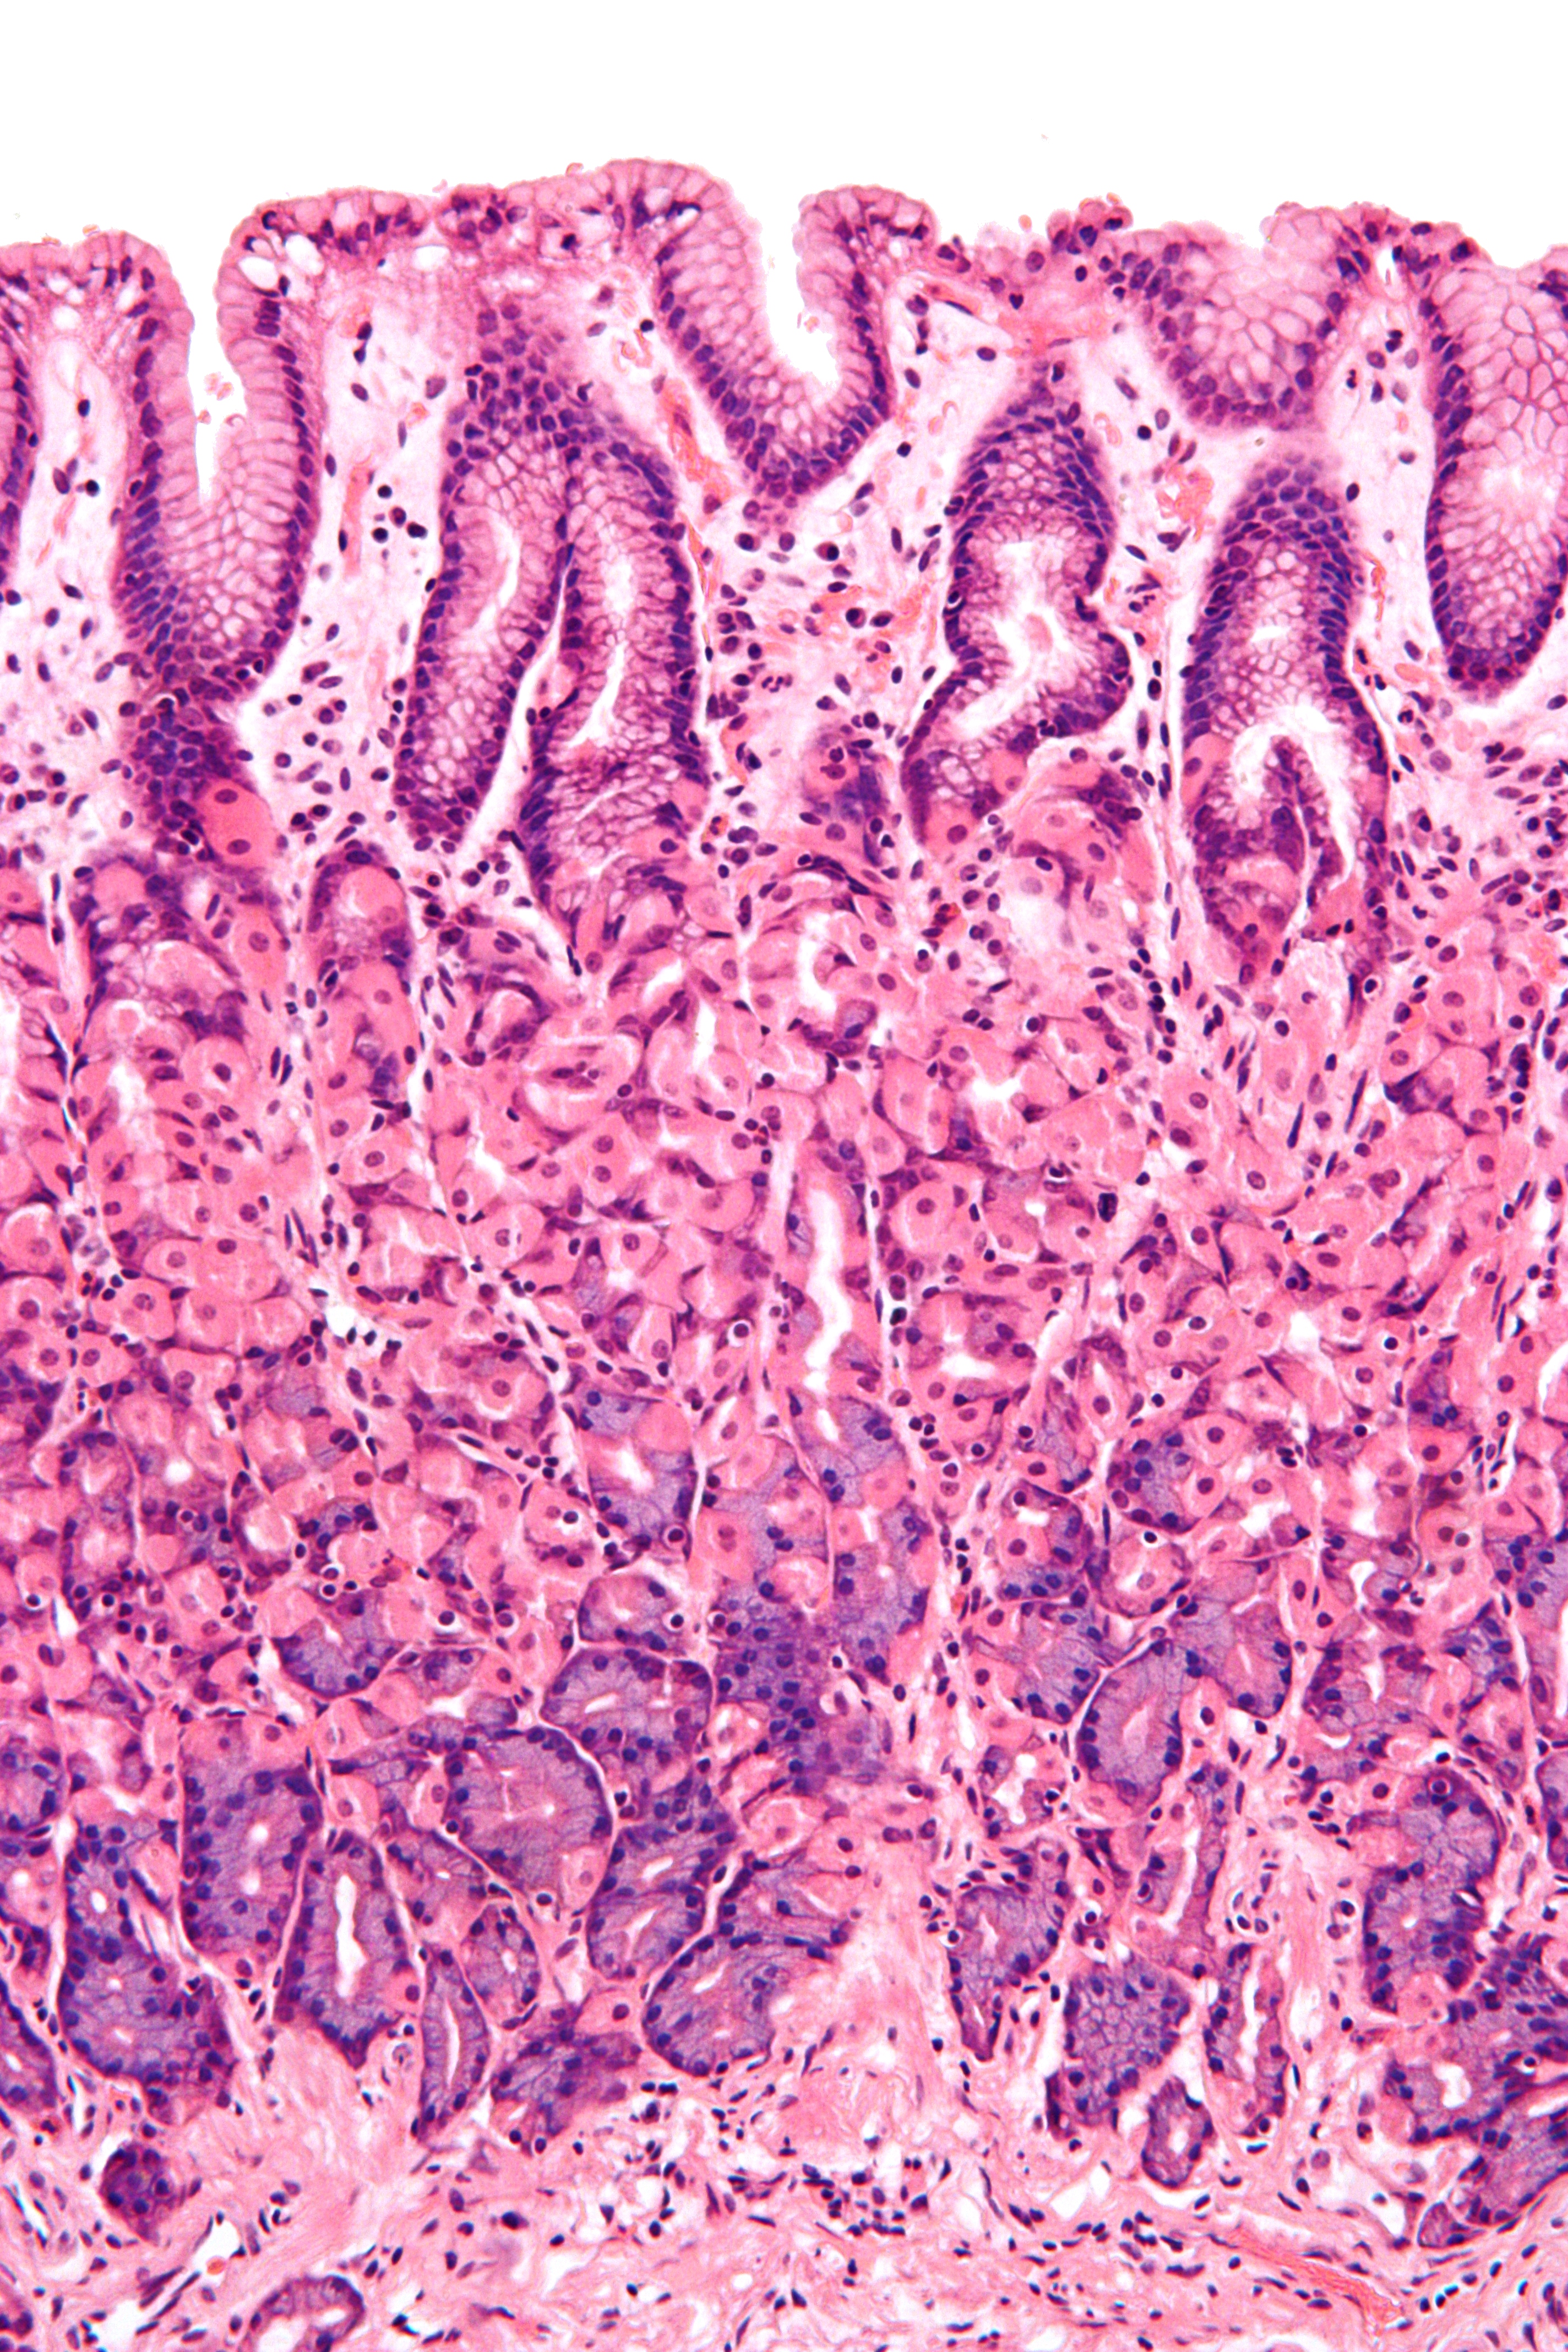

점막은 위장관의 가장 안쪽 층으로, 소화관 내부 공간(내강)을 둘러싸고 소화된 음식물(키메)과 직접 접촉한다. 점막은 세 개의 층으로 구성된다.[1]점막 상피는 많은 술잔 세포를 가진 선상피이다. 술잔 세포는 점액을 분비하여 음식물 통과를 돕고 소화 효소로부터 장벽을 보호한다. 소장에는 융모가 있어 표면적을 넓힌다. 융모 속 유미관은 림프계와 연결되어 지질과 조직액 제거를 돕는다. 미세 융모는 융모 상피에 존재하여 흡수 면적을 더욱 넓힌다. 대장에는 융모가 없고 수천 개의 샘이 있는 평평한 표면이 관찰된다. 상피 아래에는 근섬유아세포, 혈관, 신경, 여러 면역 세포를 포함하는 고유층과 장의 지속적인 연동 운동 및 분절 운동을 돕는 점막근층이 있다.

2. 1. 2. 상피의 종류

점막의 상피 내벽은 위장관에 따라 다르다.[1] 상피는 여러 층의 세포로 구성되어 있으면 중층, 한 층의 세포로 구성되어 있으면 단층이라고 한다. 세포의 모양은 기둥 모양이면 원주형, 편평하면 편평형이라고 부른다.

- 소장에서 상피는 흡수를 위해 특화된 단층 원주형이다. 원형 주름과 융모로 구성되어 있으며, 장세포에는 미세 융모가 있다. 미세 융모는 흡수 면적을 증가시키는 가장자리 띠를 형성한다. 회장에는 때때로 고유층에 페이어판이 있다. 브루너샘은 십이지장에서 발견되지만 소장의 다른 부분에서는 발견되지 않는다.[1]

- 잘록창자에서 상피는 단층 원주형이며 융모가 없다. 점액을 분비하는 술잔 세포도 존재한다.[1]